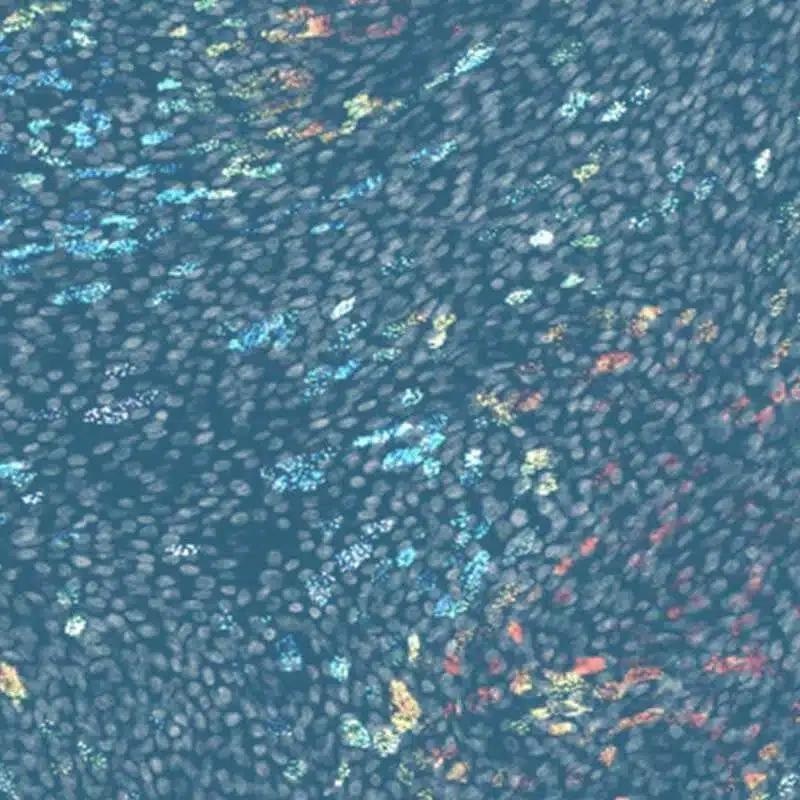

Drug metabolism can be studied using in vitro liver, lung, and stomach models. These robust human models perfectly mirror the complexity of the physiological milieu, representing a significant leap in DMPK research.